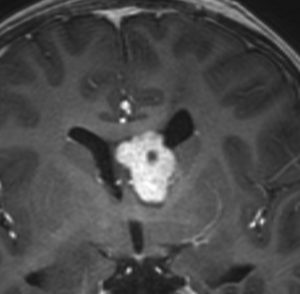

10歳の時に水頭症による頭痛と嘔吐で発症しました。結節性硬化症に合併したSEGAです。生検術,内視鏡手術,開頭術を受けて腫瘍を小さくして,その後にエベロリムスの投与を受けていました。これはエベロリムス投与後の画像です。この腫瘍にさらにエベロリムスの投与を続けるかという疑問があります。やめれば再燃することが多いからです。

結論として,これは完全摘出できるので摘出した方がいいです。なぜならそれでこの腫瘍は治癒するからです。右のFLAIR画像で見られるように発生部位となる尾状核のところでは一見,脳組織との境界が不明瞭にみえるのですが,腫瘍はある程度の硬さがあるので脳組織との区別をすることができて,完全摘出できるものです。